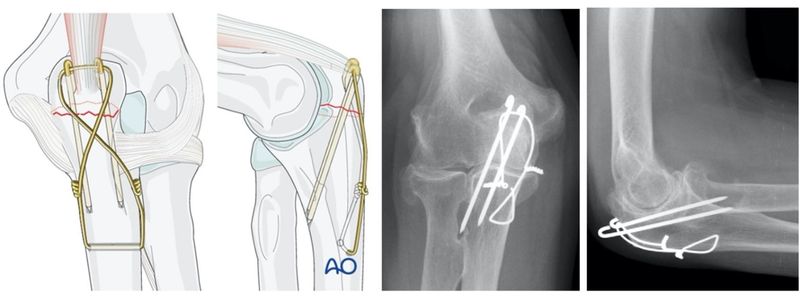

2. Κάταγμα ωλεκράνου

Το ωλέκρανο είναι το πίσω μέρος της ωλένης και αποτελεί τμήμα της άρθρωσης. Τα κατάγματα εδώ είναι συνήθως ενδαρθρικά.

Αντιμετώπιση:

- Σταθεροποίηση με μεταλλικές βελόνες και σύρματα ή πλάκες και βίδες

- Άμεση κινητοποίηση για αποφυγή συγκάμψεων